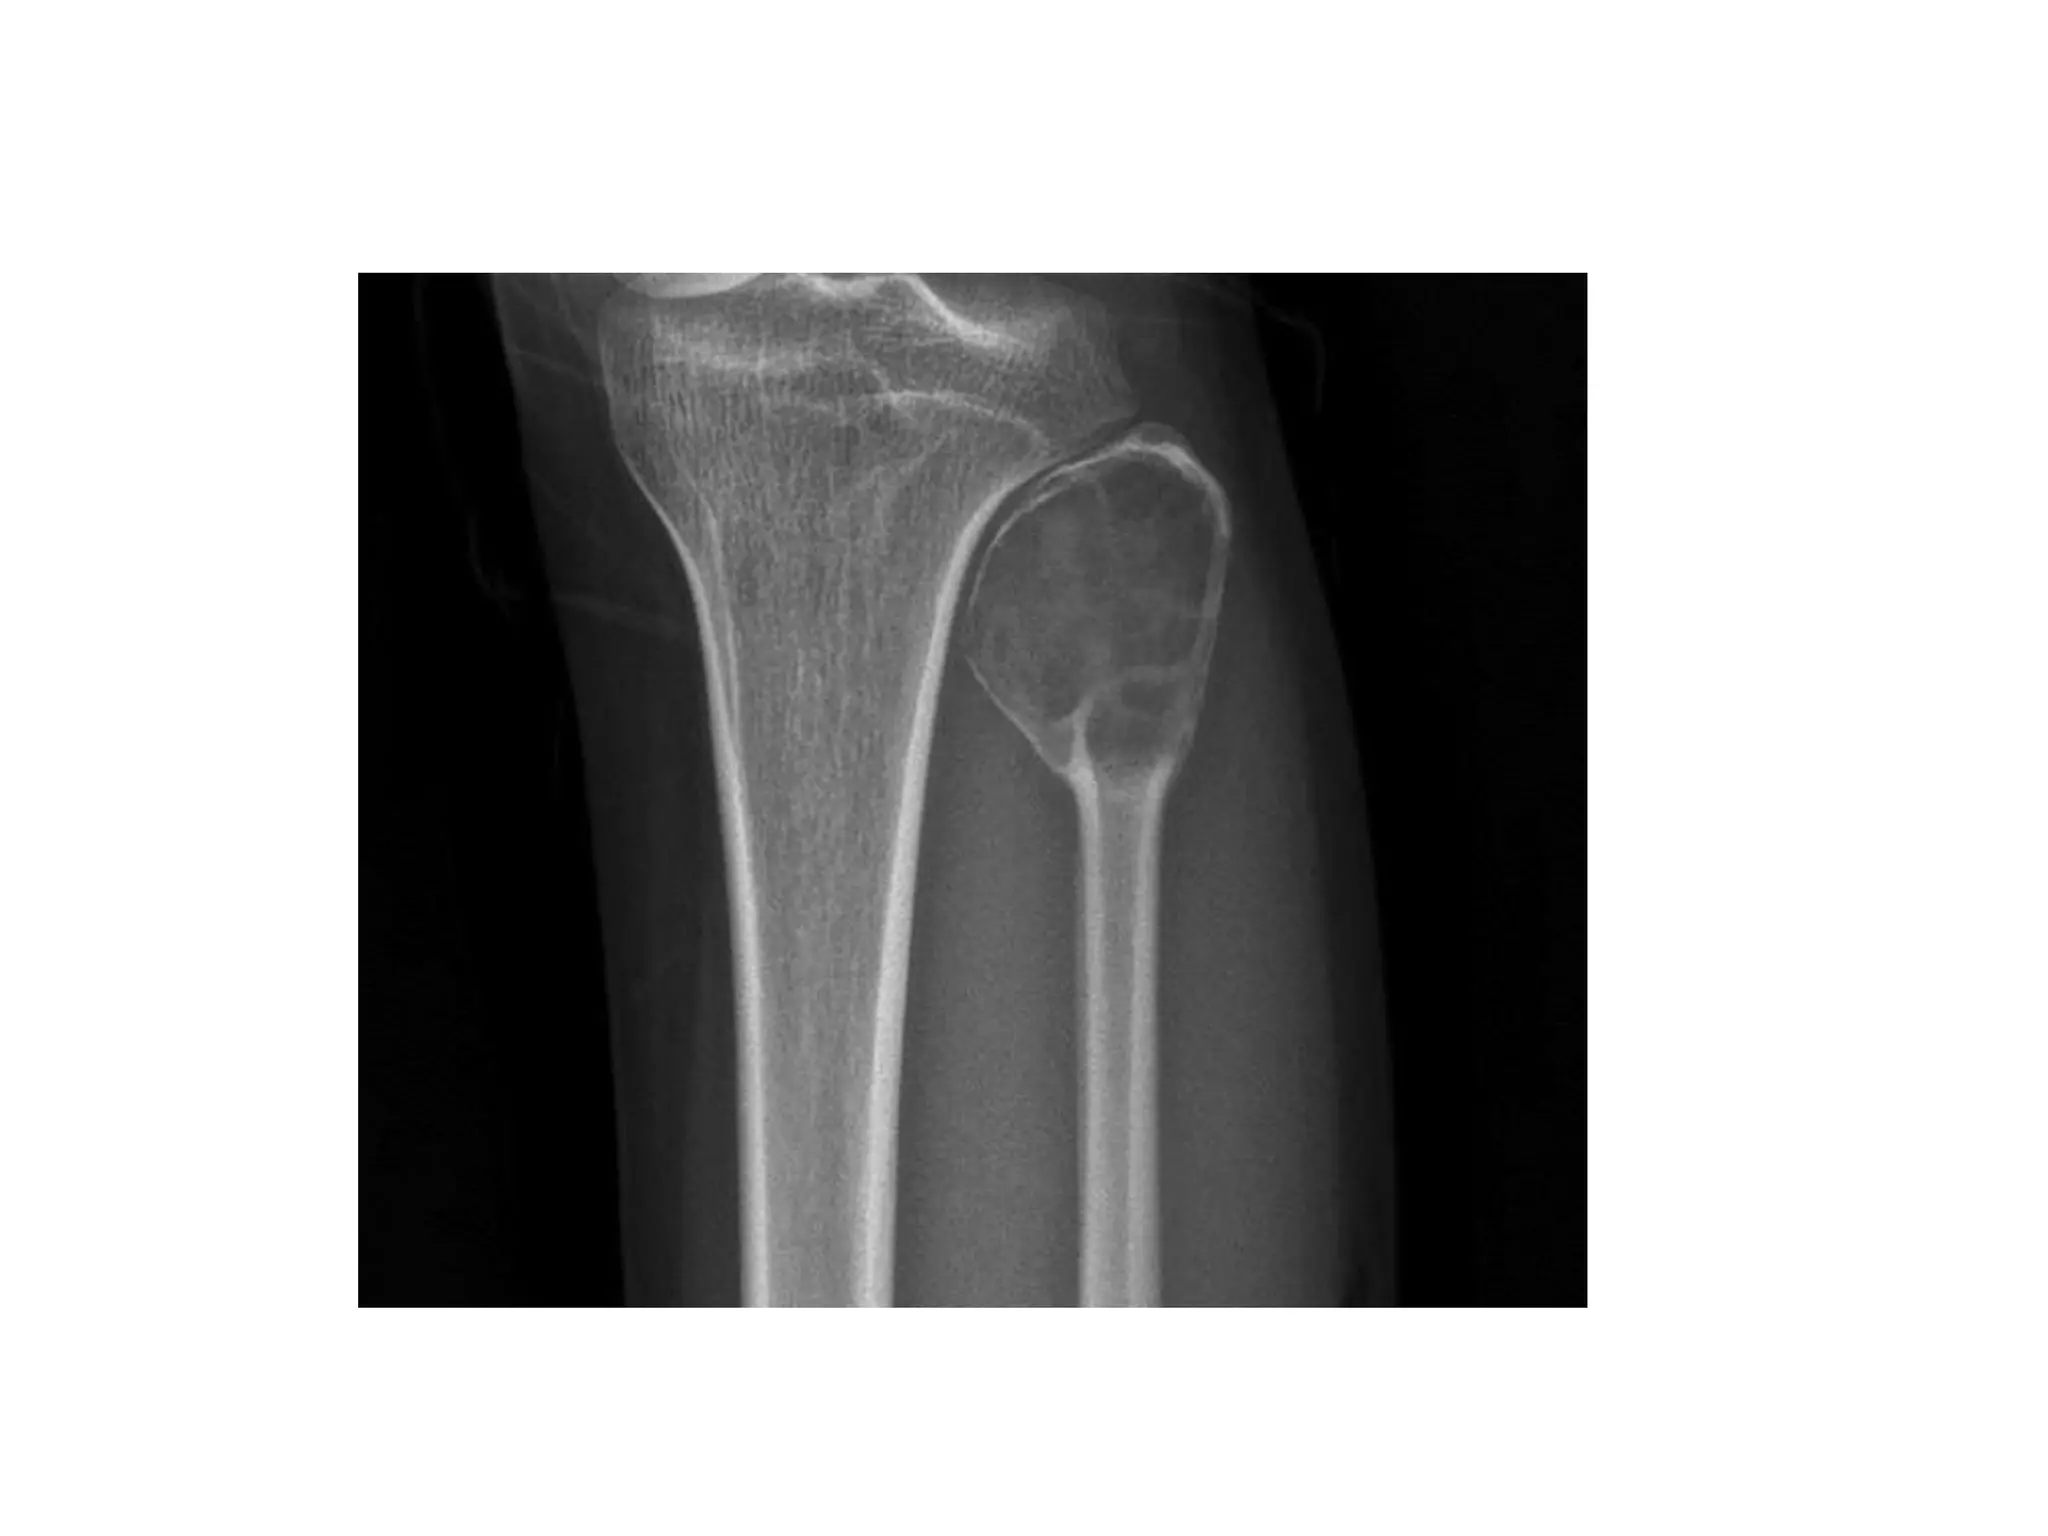

CHONDROBLASTOMA

• These are benign tumours of childhood.

long bones.

common in males.

35 and exceptional before the age of 10.

effusion or stiffness.

• They appear as a round or oval lytic lesion ranging in size from 1 to

7 cm on X-ray.

physis. The cortex may be expanded but often is not breached

• Histologically, they appear as ‘wet-sawdust’ with areas of chondroid

• The presence of ‘chicken-wire’ calcification is pathognomonic.

• The majority of cases can be treated with simple curettage with or

plate.

CT guidance.

cases.

• More aggressive, en-bloc resection may be required for recurrent